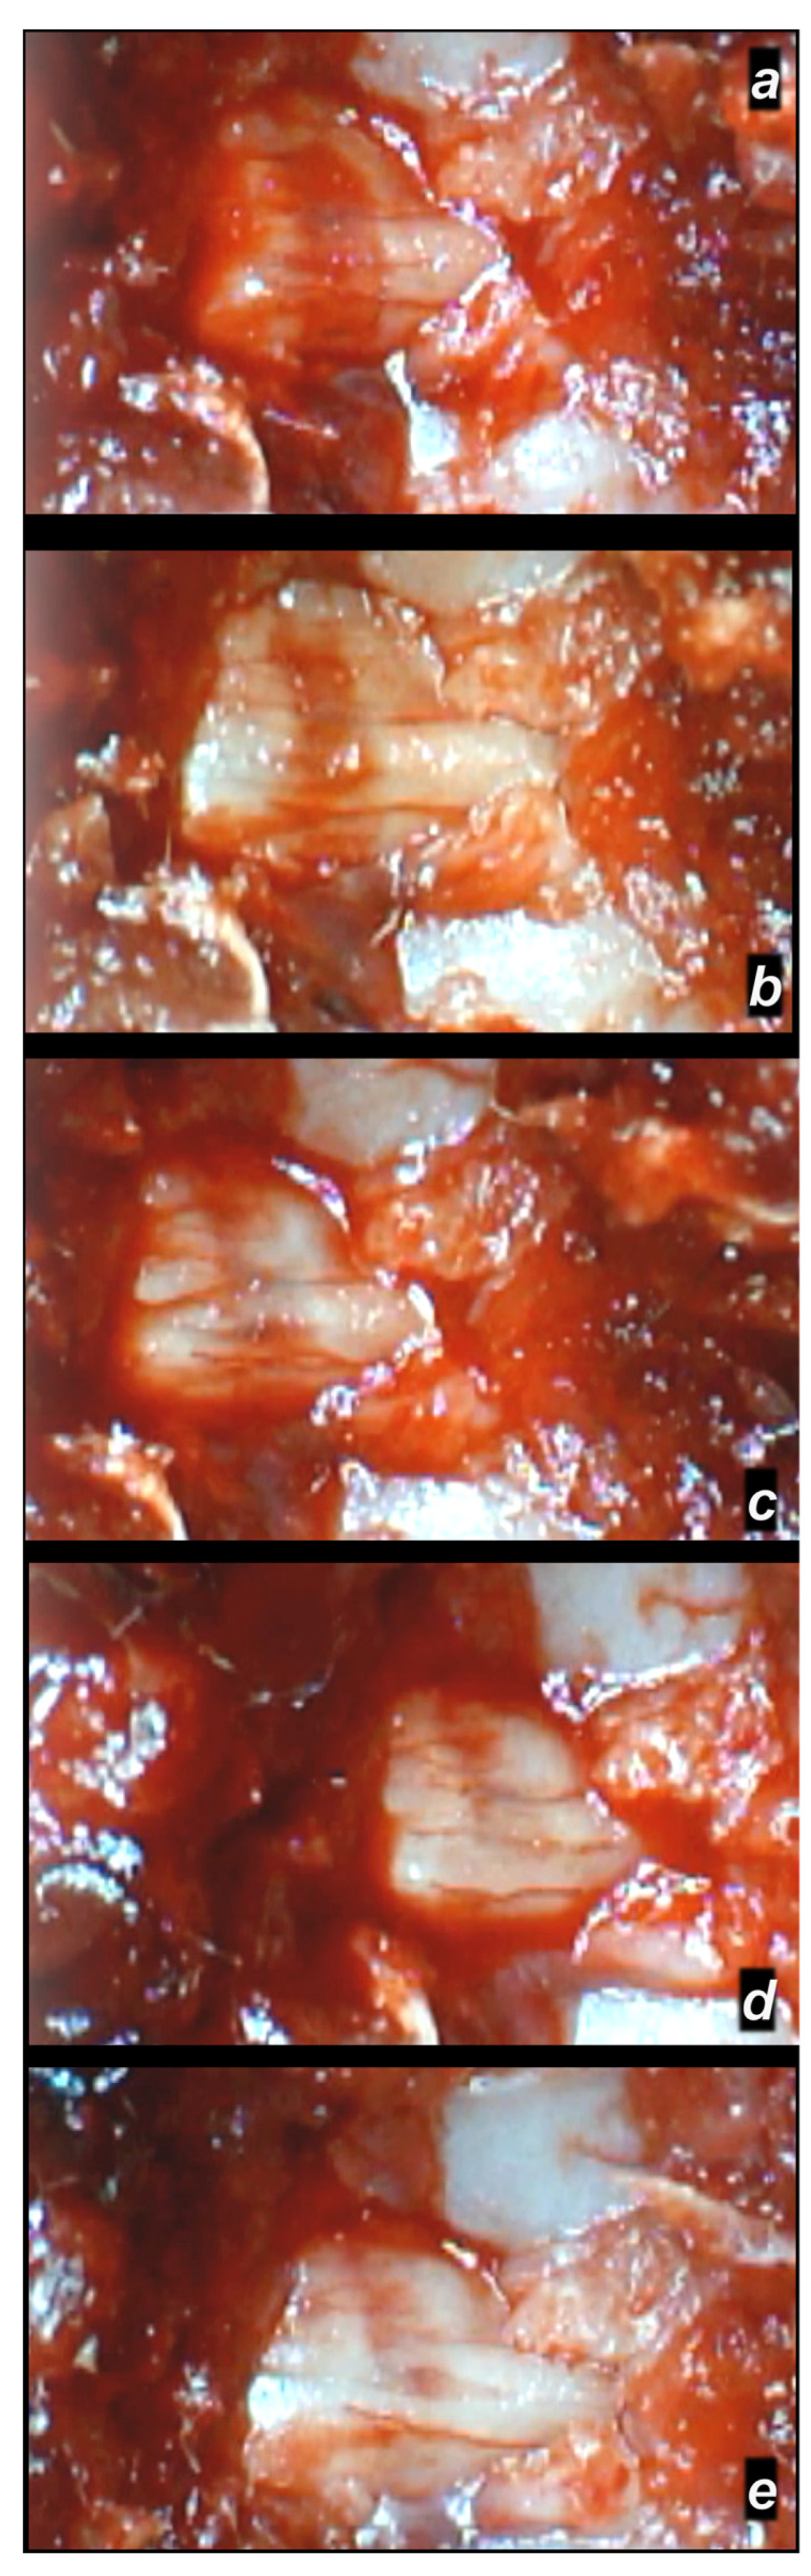

3.2.2. Delayed Post-Injury Course, Immediate Effect

3.2.3. Delayed Post-Injury Course, Long-Term Effect